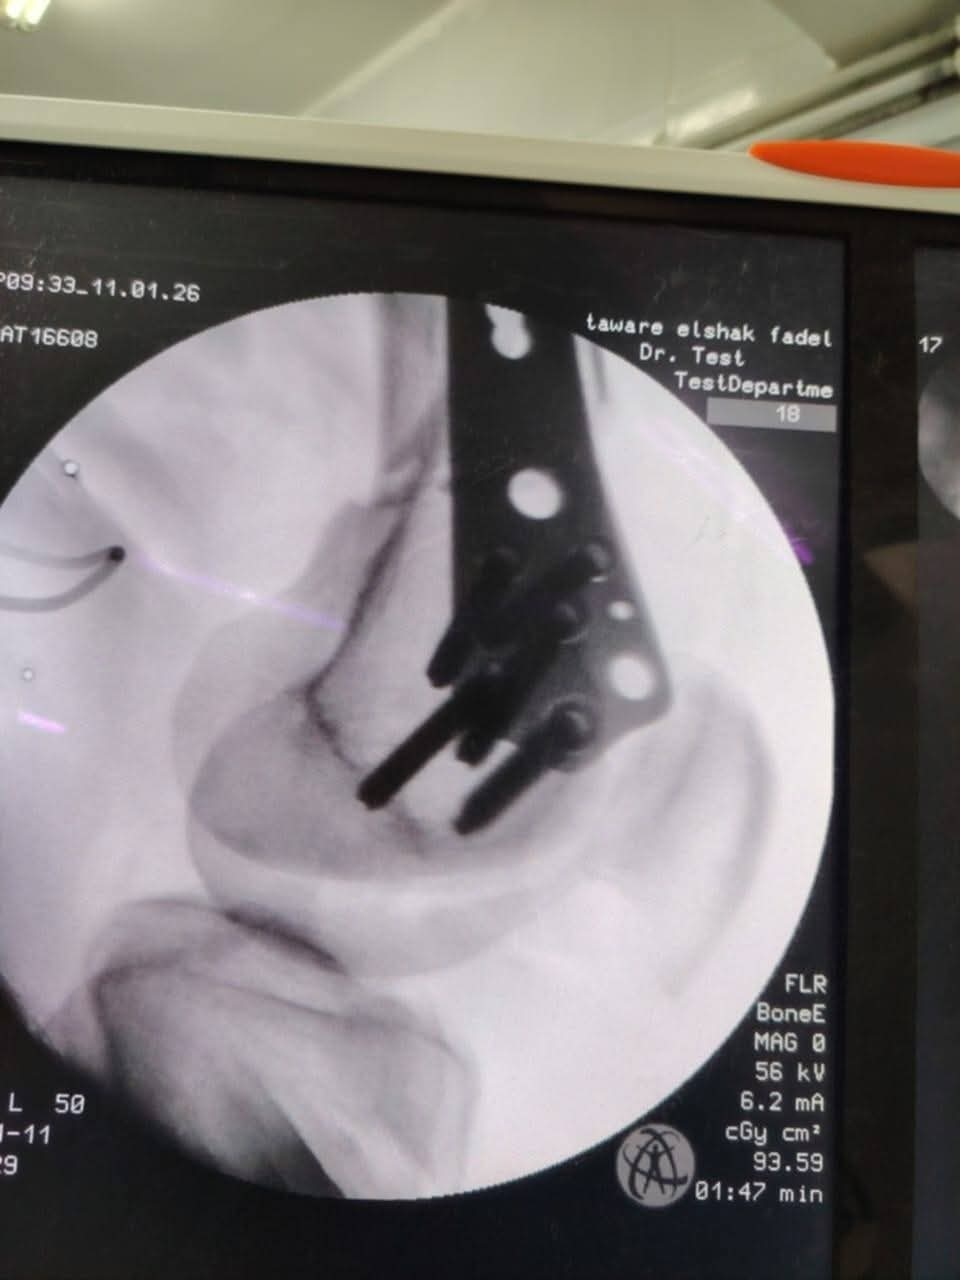

في استمرار لنجاحات المنظومة الطبية داخل مستشفى طوارئ "الشيخ فضل"، نجح الفريق الطبي بقسم العظام في إجراء جراحة دقيقة ومعقدة لرد وتثبيت كسر "متفتت" بأسفل عظمة الفخذ الأيمن لشاب يبلغ من العمر 35 عاماً، إثر سقوطه من علو.

اعتمد الفريق الطبي في هذه الجراحة على تقنية إزاحة الشريحة تحت العضلات (MIPO) عبر فتحات جراحية صغيرة جداً، وهي من أحدث التقنيات العالمية في جراحات الكسور؛ حيث تضمن الحفاظ على الأنسجة والعضلات، وتقلل من احتمالات النزيف والعدوى، مما يسرع من عملية الالتئام وعودة المريض لممارسة حياته الطبيعية بكفاءة عالية.

تم تثبيت الكسر دون الحاجة لفتح جراحي واسع عن طريق استخدام تقنية MIPO، مما يحافظ على التروية الدموية للعظم.